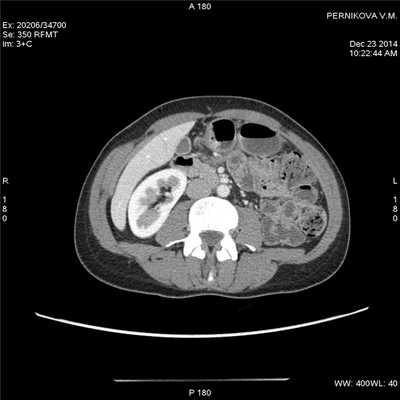

(Слева) На КТ, выполненной мужчине 37 лет с обострением хронической симптоматики (боль в животе и диарея), определяется растяжение некоторых сегментов проксимальных отделов тонкой кишки.

(Справа) На КТ у этого же пациента определяется большее количество растянутых петель тонкой кишки, слизистая оболочка которых интенсивно накапливает контраст на фоне подслизистого отека. Визуализируются также группы умеренно увеличенных лимфатических узлов брыжейки (Слева) На КТ у этого же пациента визуализируются два сегмента воспаленной тонкой кишки, разделенные неизмененными участками - классические «прерывистые» поражения при болезни Крона. Обратите внимание на полнокровные прямые сосуды, кровоснабжающие более дистальные отделы воспаленного кишечника.